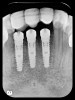

Radiographic evidence of external root resorption on tooth No. 26 and periapical radiolucencies with a history of prior endodontic treatment, including apicoectomies, were present on the mandibular central incisors (Figure 2).

Figure 2  Initial periapical radiographs showing failed endodontic treatment of Nos. 24 and 25, and root resorption, No. 26.

Figure 2